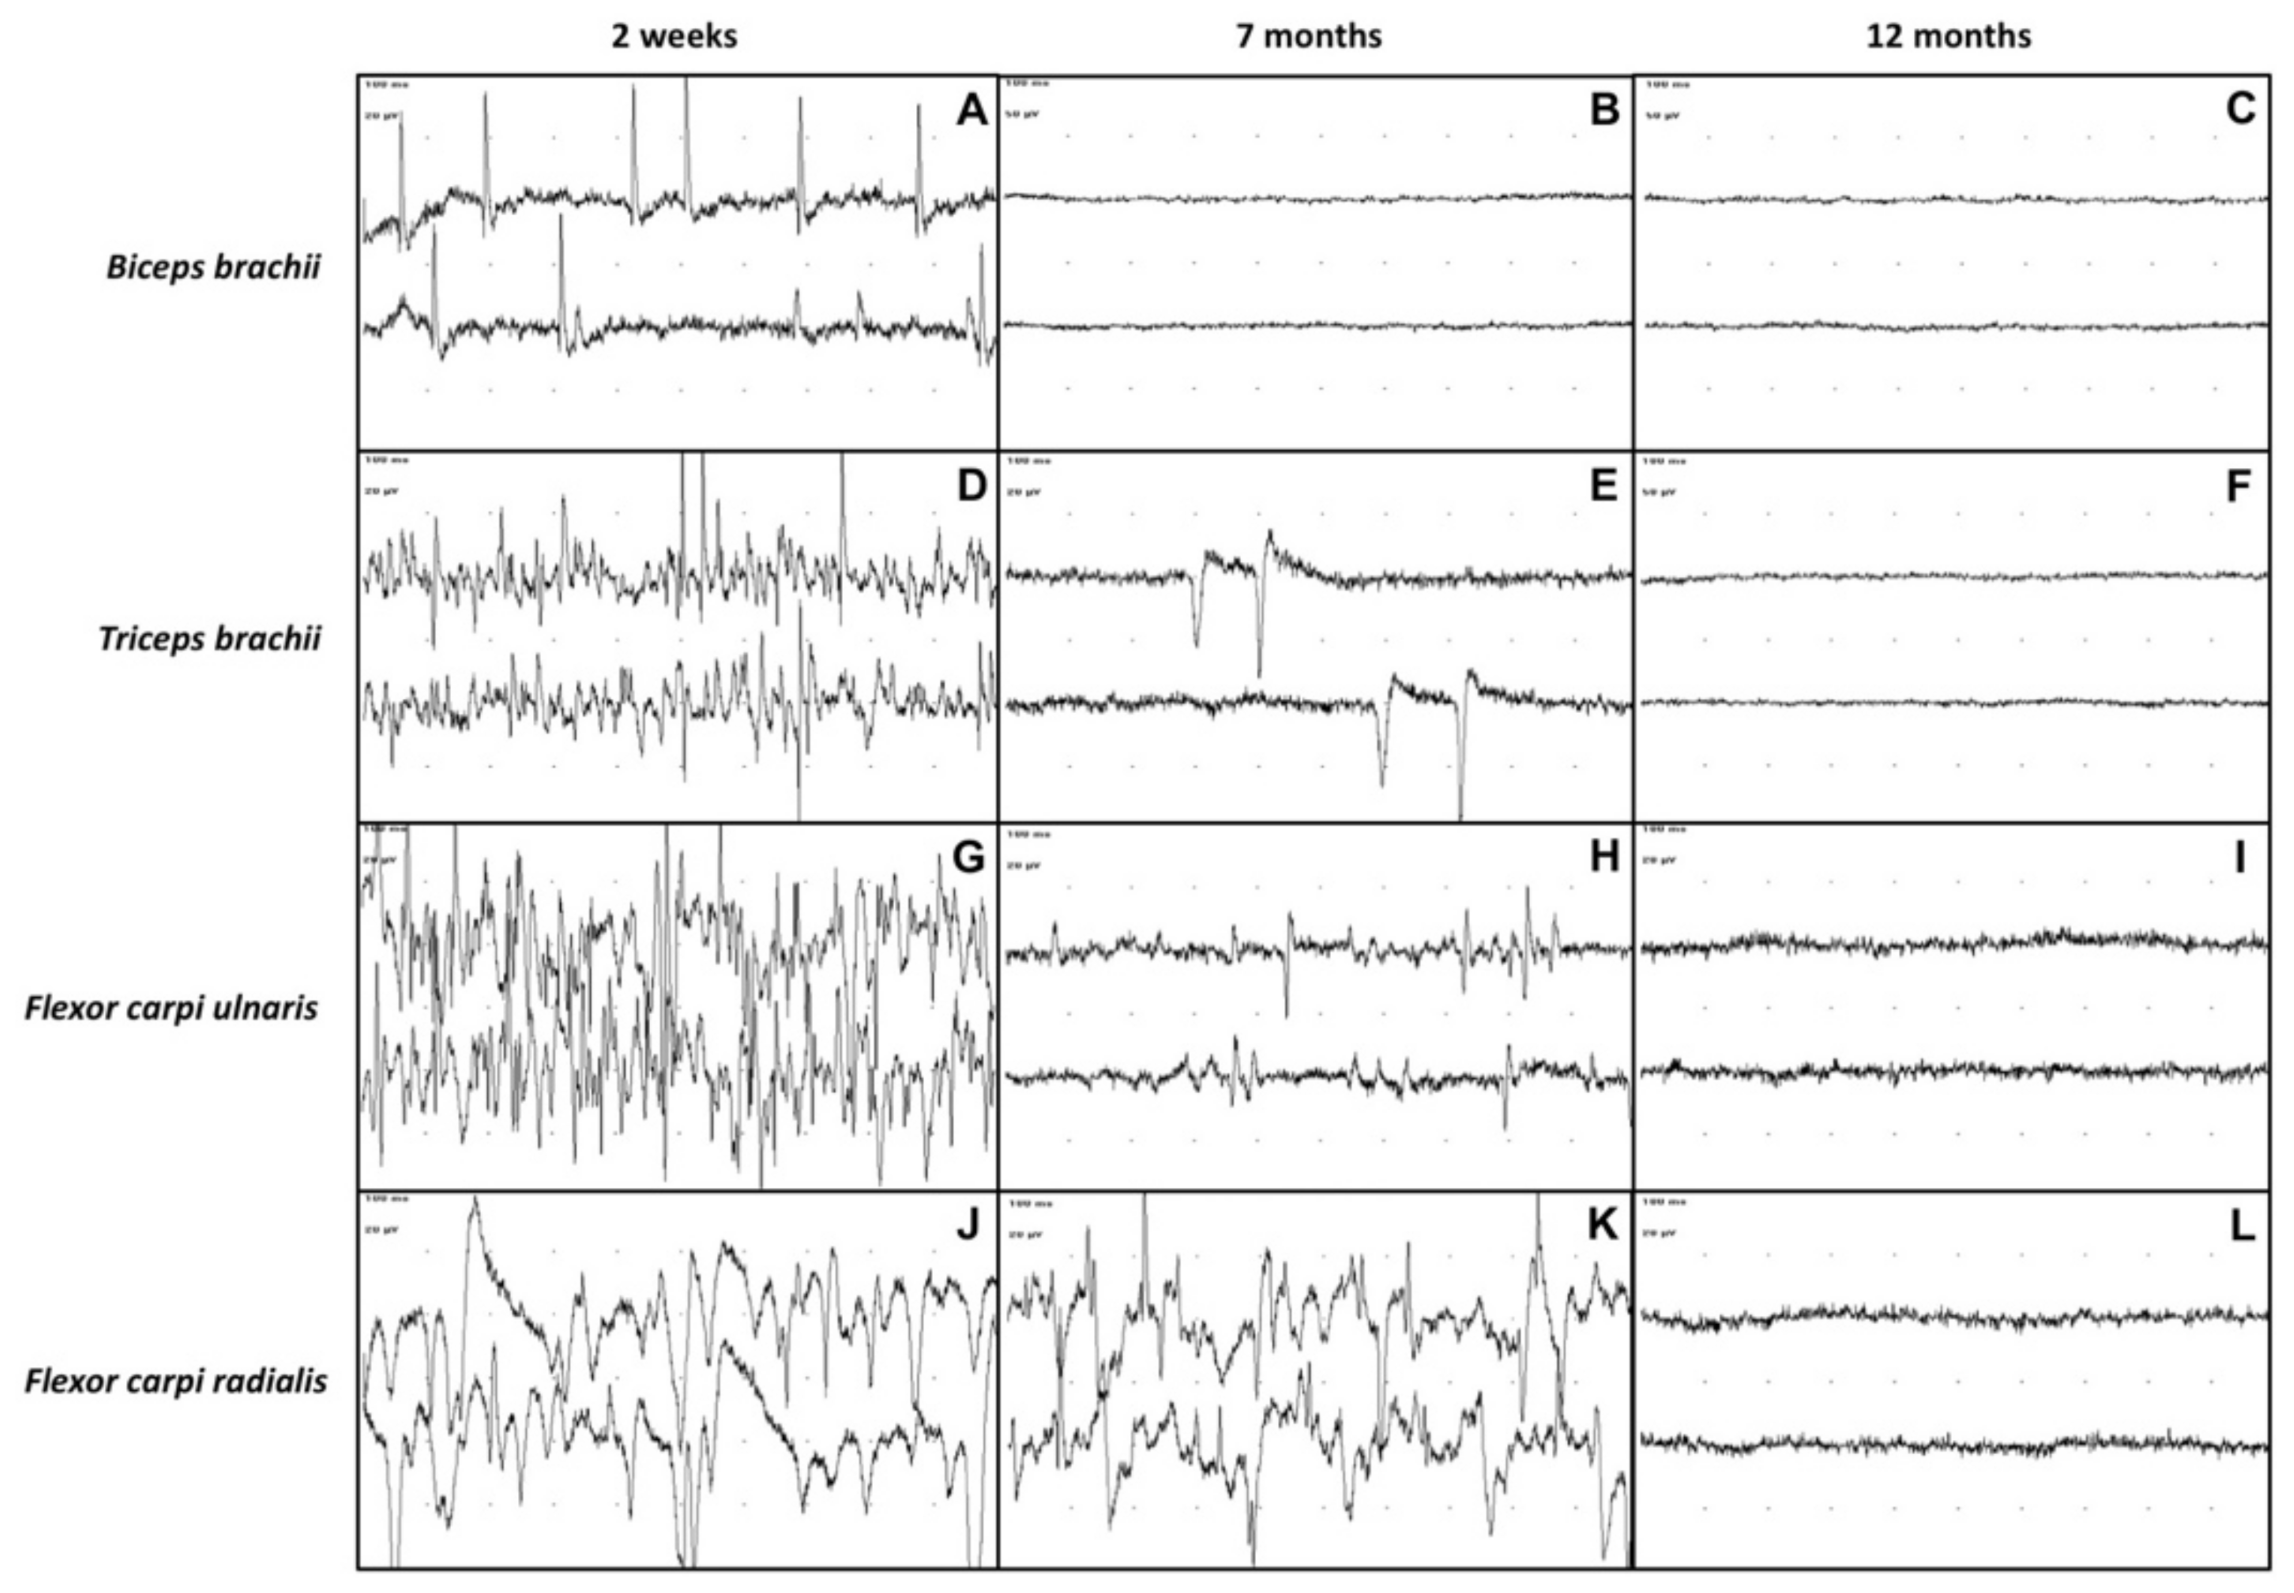

At the first electrodiagnostic investigation, performed 2 weeks after admission, EMG revealed the presence of moderate to severe spontaneous pathologic activity in all the evaluated muscles of the left thoracic limb (Figure 3A,D,G,J).

At 7 months after admission, the calf was able to stand on four legs, although the gait was still quite unsteady. The flexor and extensor carpi radialis reflexes of the affected limb, as well as the postural reactions, were still slightly reduced. The sensory testing detected nociception on the entire limb and cutaneous trunci reflex was present bilaterally. The triceps were increased in volume. The cutaneous trunci reflex was bilaterally present and no miosis was observed in the left eye. On EMG, the only muscles showing spontaneous pathologic activity at the EMG were the triceps brachii, flexor carpi ulnaris and flexor carpi radialis (Figure 3E,H,K). Moreover, the pathologic activity was less intense than in the previous observation. Interestingly, the EMG activity of the biceps brachii was completely normal (Figure 3B). The motor NCS of the left thoracic limb showed an increase in the CMAPs amplitude and area (Figure 4B,E,H), compared with the previous NCS.

Twelve months after admission, the EMG detected no spontaneous pathologic activity in the affected limb (Figure 3C,F,I,L). The CMAPs amplitude and area of the left thoracic limb’s nerves had further increased compared to the previous recordings and were similar to those of the healthy right thoracic limb (Figure 4C,F,I). At clinical examination, the animal exhibited completely normal posture and motor functions. After a thorough neurological investigation, the animal was deemed clinically recovered.

Figure 3. EMG recording of the left thoracic limb’s muscles (biceps brachii, triceps brachii, flexor carpi ulnaris, flexor carpi radialis) at 2 weeks, 7 months and 12 months after admission. Sweep speed: 10 ms/div. Biceps brachii muscle at 2 weeks (A), 7 months (B) and 12 months (C) after admission. Triceps brachii muscle at 2 weeks (D), 7 months (E) and 12 months (F) after admission. Third row: Flexor carpi ulnaris muscle at 2 weeks (G), 7 months (H) and 12 months (I) after admission. Flexor carpi radialis muscle at 2 weeks (J), 7 months (K) and 12 months (L) after admission. An evident reduction of spontaneous pathologic activity can be observed at 7 months after admission up to normalization of EMG tracings in all the recorded muscles at 12 months after admission.